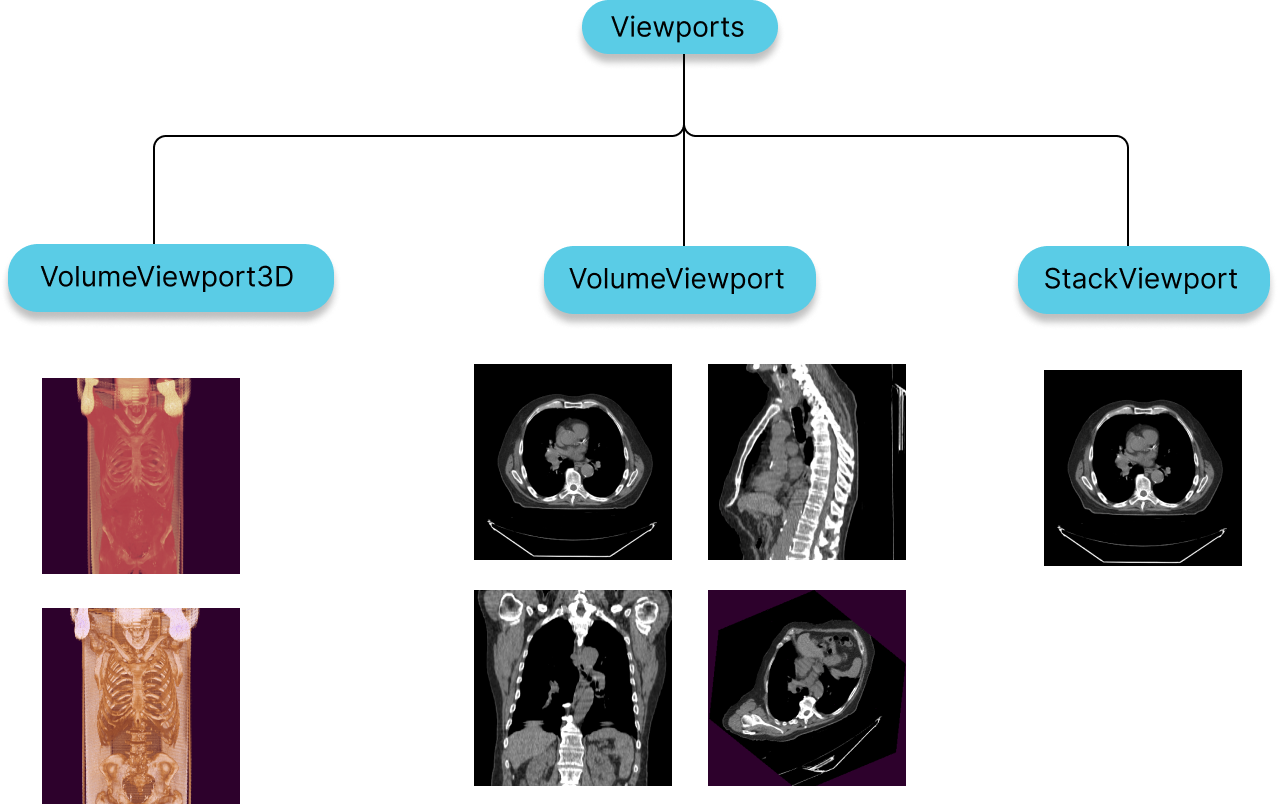

Viewports

StackViewport

- Suitable for rendering a stack of images, that might or might not belong to the same image.

- Stack can include 2D images of various shapes, size and direction

VolumeViewport

- Suitable for rendering a volumetric data which is considered as one 3D image.

- Having a VolumeViewport enables Multi-planar reformation or reconstruction (MPR) by design, in which you can visualize the volume from various different orientations without addition of performance costs.

- For having image fusion between two series

3D Viewport

- Sutiable for actual 3D rendering of a volumetric data.

- For having different types of presets such as Bone, Soft Tissue, Lung, etc.

Both StackViewport and VolumeViewport, VolumeViewport3D are created via the RenderingEngine API.